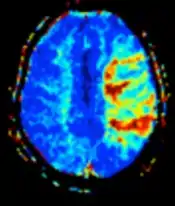

Perfusion weighted (PWI) Dynamic susceptibility contrastDSCGadolinium contrast is injected, and rapid repeated imaging (generally gradient-echo echo-planar T2 weighted) quantifies susceptibility-induced signal loss.[65] In cerebral infarction, the infarcted core and the penumbra have decreased perfusion (pictured).[66]